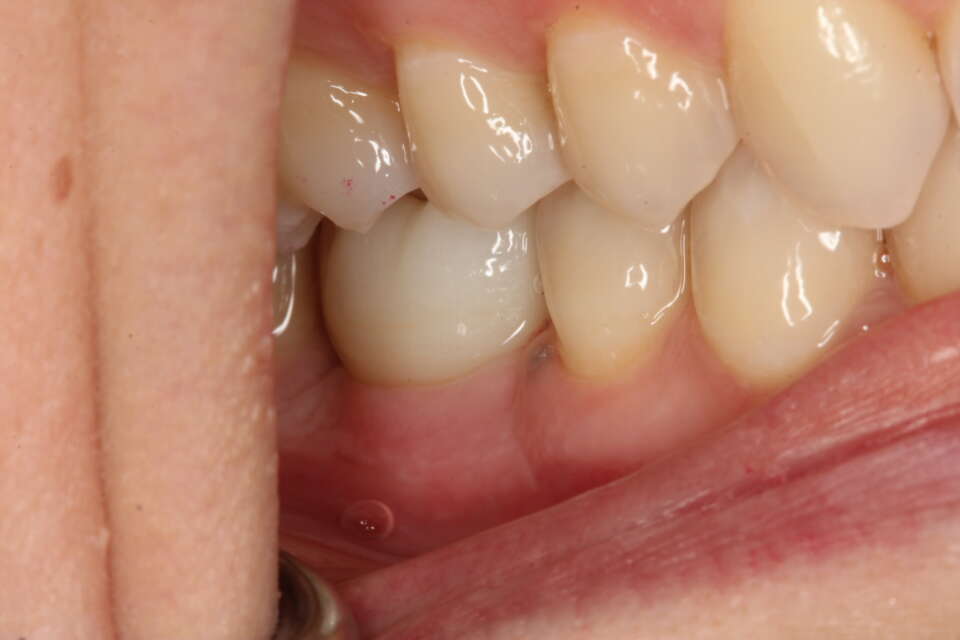

Before Treatment

IMG 6913

IMG 6908

A missing back molar which affects eating and everyday function.